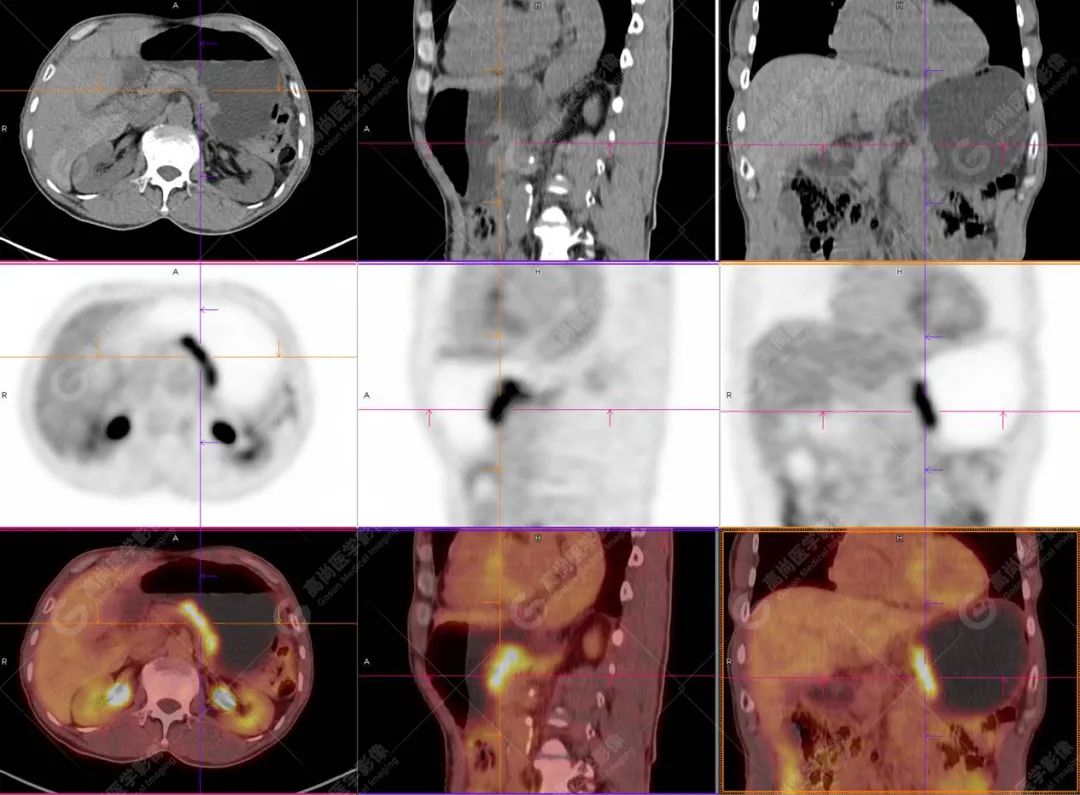

HAS 的影像学表现具有一定特征。CT 上多表现为胃壁不规则明显增厚,平均厚度超过 3.0 cm,肿瘤多向腔内生长形成较大的软组织肿块,易合并出血、坏死,密度不均匀,边界不清晰,常向周围浸润,累及肝脏、胰腺、食管等邻近器官,增强扫描呈轻至中度不均匀强化;腹腔淋巴结转移和肝脏转移常见,肝转移瘤以多发较大的低密度肿块为主,与原发性肝癌(HCC)动态增强扫描方式相似,均呈「快进快出」;易侵犯局部血管,较常见到大的分支如门静脉或脾静脉癌栓形成。

综上所述,HAS 好发于中老年男性,典型表现为胃窦或胃体小弯侧偏心性厚壁肿块,常伴血清 AFP 指标升高且早期易出现胃周淋巴结和肝脏转移。影像学表现符合胃癌且临床伴有血清 AFP 指标明显升高的患者需要考虑到 HAS 的可能。当发生肝转移时与原发性肝癌的主要鉴别点为是否有肝炎及肝硬化病史。